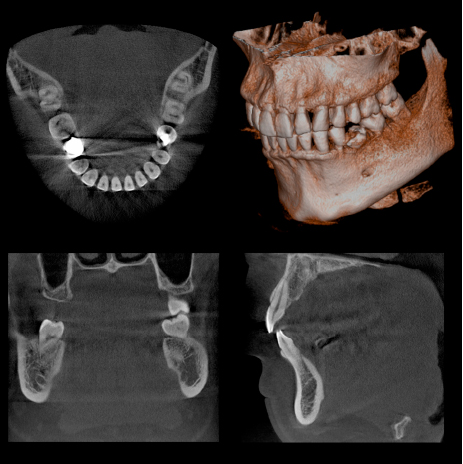

CTを導入いたしました

当院では歯科での普及率が6%程度と言われる、CT(コンピュータ断層撮影機)を導入いたしました。

当院では歯科での普及率が6%程度と言われる、CT(コンピュータ断層撮影機)を導入いたしました。

通常のX線撮影では、歯やアゴの骨の状態を二次元でしか確認できないため、色々な病状(歯の根の病気や歯周病の病状)を見落としてしまう可能性は否 定でき ません。CTを撮影することによって、あらゆる方向から三次元で歯やアゴ骨の状態を確認可能なため、詳細な診断が可能になります。

撮影時間も9.4秒と極めて短く、放射線の被曝量は、医科用CT撮影(頭部)の1/77~1/23以下です。

限られた病変(歯の神経の治療、歯周病の治療、親知らずの抜歯など)においては保険適用での撮影が可能です。

また、インプラントの手術をする際には、アゴの骨の状態を診査するには必ずCT撮影が必要であり、その後の定期診査にも非常に有効です。

医科用CT撮影に比べると少ないながらも、被爆のデメリットもありますので、必要に応じて使用し、診査・診断に大いに役立てていきたいと思います。